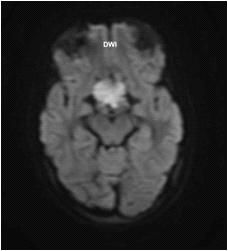

A non-contrast CT brain persists in being the first choice of imaging modality in the initial diagnosis of

ICH, as it is readily available, accessible and fast9. A non-contrast CT brain can reveal and differentiate between the several intracranial & extracranial pathology, including Ischemic Stroke, Subarachnoid Haemorrhage, and ICH. It can also demonstrate the extension of the haemorrhage regarding surrounding oedema, size, intraventricular clot extension, the mass effect (Fig 1) and raised intracranial pressure.

Spontaneous or acute ICH appears on the CT head as an area of hyperdensity within the Parenchyma (Fig 2) or extended into the ventricle (Fig 3), with surrounded hypodense perivascular oedema.